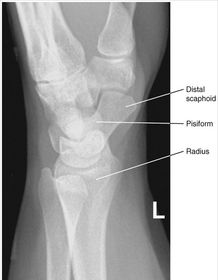

| PA Wrist | wrist externally rotated - joint spaces closed, proximal metacarpals superimposed, carpals superimposed radiocarpal joint is closed |

| Oblique Wrist | over rotation radial styloid is not seen in profile |

| Lateral Wrist | under rotation - radius and ulna are not superimposed, hand is internally rotated |

| PA Wrist | ANATOMY: all carpals including midmetacarpals and distal radius/ulna CRITERIA: true PA is marked by symmetry of proximal metacarpals carpals should be free of superimposition of the metacarpals and radius/ulna POSITIONING: CR perpendicular @ midcarpals |

| Oblique Wrist | ANATOMY: carpals on lateral side of wrist, scaphoid CRITERIA: scaphoid well demonstrated 45 degree obliquity POSITIONING: CR perpendicular @ midcarpals |

| L | CRITERIA: radius/ulna should be superimposed thumb should be forward metacarpals superimposed POSITIONING: CR perpendicular @ midcarpals |